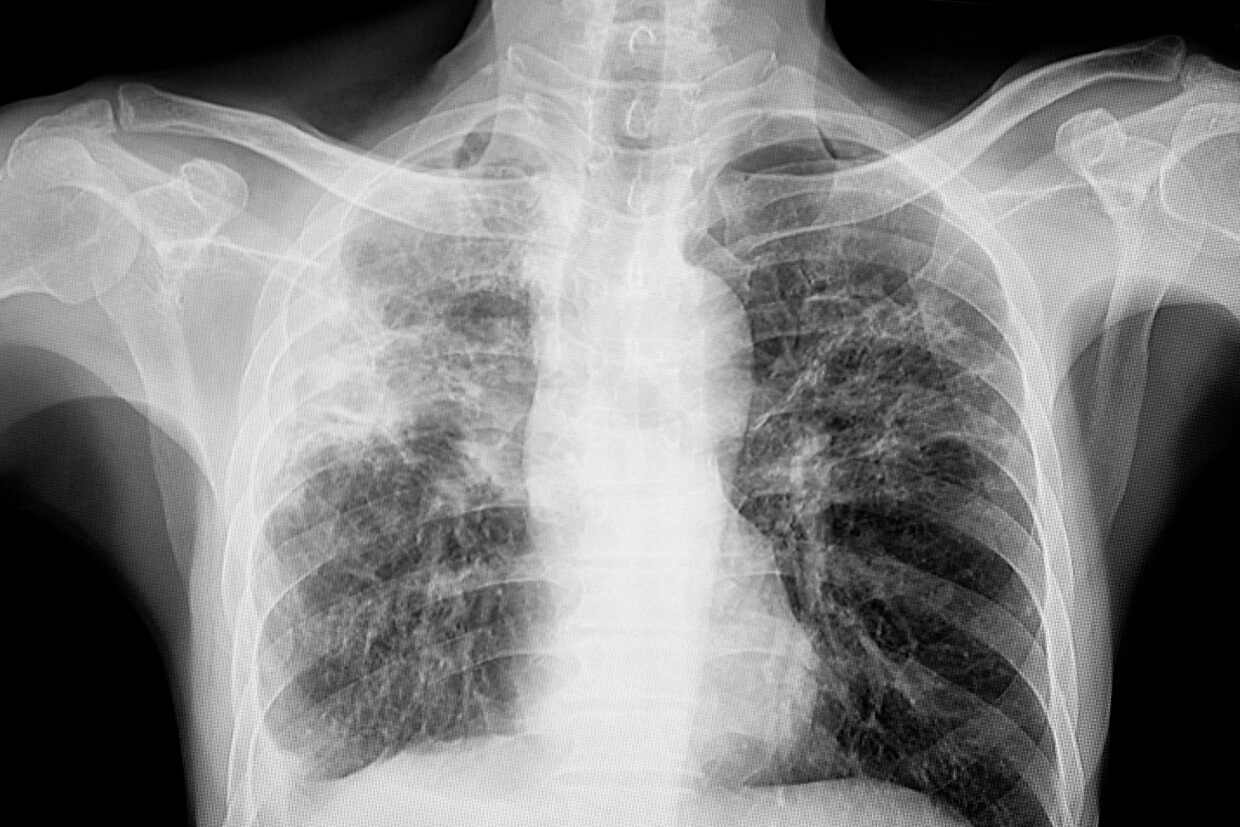

Early symptoms signal pulmonary TB risk

Dr Lo emphasised that one of the earliest and most common signs of active pulmonary TB is a persistent cough lasting more than two weeks. Other symptoms include night sweats, low-grade fever, fatigue, unintentional weight loss, and in more advanced cases, coughing up blood-stained sputum or chest pain.

“Symptoms can develop gradually, so some people delay seeking care, thinking it’s just a cold. But early detection is important, not only for successful treatment but also to reduce the risk of infecting others,” he elaborated. (CDC)